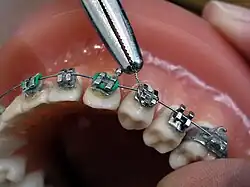

Im November 1895 entdeckte Wilhelm Conrad Röntgen die später nach ihm benannten Röntgenstrahlen, die die Untersuchung des Kiefers vereinfachten. Als Mittel zur örtlichen Betäubung von Zahnschmerzen wurde im Jahre 1905 das Lokalanästhetikum Procain von den deutschen Chemikern Alfred Einhorn und Emil Uhlfelder entwickelt, die dem Wirkstoff den Namen Novocain (lateinische Wortschöpfung für „Neues Cocain“) zuordneten. Damit waren die Grundlagen für eine moderne Diagnostik und Therapie gelegt. Die Zahnheilkunde erlebte daraufhin einen rasanten Fortschritt: von der Entwicklung zahlreicher oralchirurgischer Verfahren bis zur Anfertigung von Zahnersatz mittels CAD/CAM-Verfahren. Parallel zum Fortschritt der wissenschaftlichen Zahnheilkunde entwickelte sich das Berufsbild, was in der Geschichte des Zahnarztberufs dargestellt wird. Daneben entwickelte sich die Tierzahnheilkunde, die sich entsprechend modifizierter Verfahren der allgemeinen Zahnheilkunde bedient.